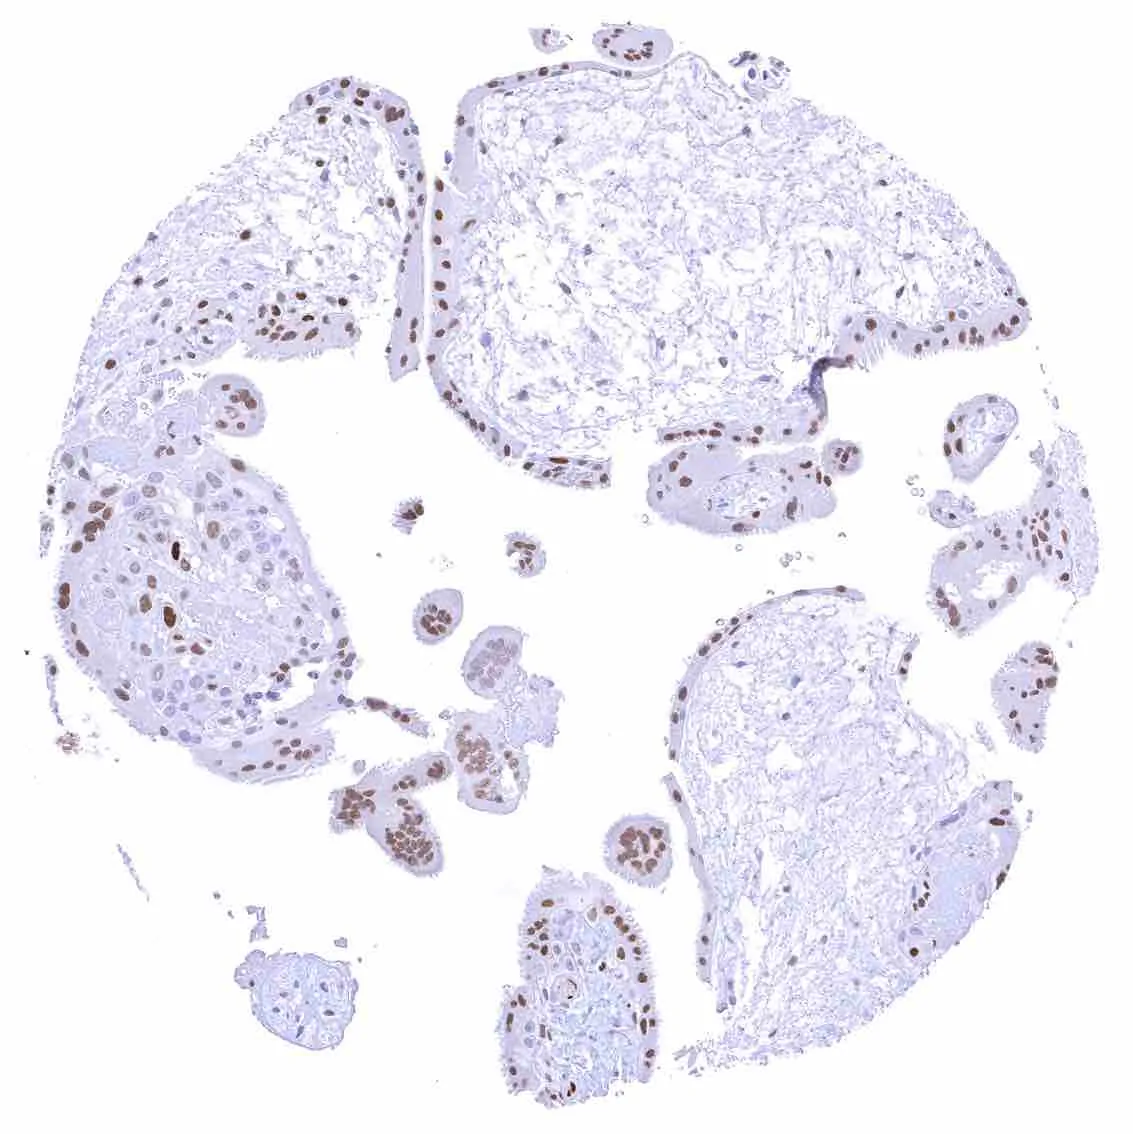

Placenta (amnion and chorion) – Moderate to strong nuclear p27 staining of most or all chorion cells. A weak to moderate nuclear p27 staining also occurs in a subset of amnion cells.

Placenta, early – Strong p27 staining of all nuclei of the syncytiotrophoblast.

Placenta, mature – Weak nuclear p27 staining of trophoblast and stroma cells.